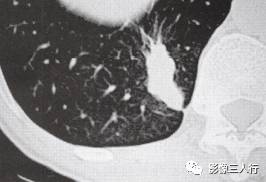

CT表现见图1。

图1 CT表现 (a)左上肺上叶周围型肺癌,边缘可见锯齿征 (b)右肺上叶前段炎性假瘤,病灶呈类圆形,密度均匀, 边缘呈锯齿状,邻近胸膜增厚粘连 (c)病灶有刀切样垂直于胸膜切线的边缘,近胸膜侧 似尖角状,后缘浅分叶,邻近胸膜增厚粘连 (d)球形肺炎